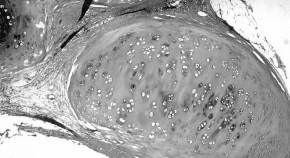

Basal-like breast cancers are associated with a poor disease-free and overall survival. The pathologic features of breast carcinomas classified by immunohistochemical and gene-expression profiling criteria are critically discussed. The authors emphasize that basal-like tumors display a spectrum of morphologic and clinical characteristics, and that the heterogenous nature of these tumors means the most prognostically relevant subsets have yet to be defined.